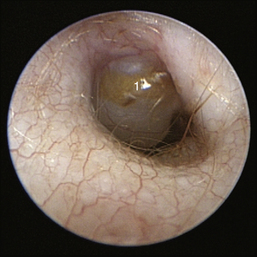

The middle ear consists of an air-filled tympanic cavity, three auditory ossicles, and the tympanic membrane. The tympanic membrane is located at a 45-degree angle in relation to the central axis of the horizontal part of the external ear canal. The tympanic membrane is a semitransparent membrane that separates the external ear canal from the middle ear, is thin in the center and thicker at the periphery, and is divided into two sections, the small upper pars flaccida and the larger lower pars tensa (Figure 20-2). The pars flaccida is the pink, small, loosely attached region forming the upper quadrant of the tympanic membrane that contains small blood vessels. The pars flaccida is usually flat; however, even in the healthy ear one may identify a bulging pars flaccida (Figure 20-3). The exception is the Cavalier King Charles Spaniel, in which a bulging pars flaccida may be indicative of a disease known as primary secretory otitis media (PSOM) (Figure 20-4).

image

Figure 20-4 Bulging pars flaccida in a Cavalier King Charles Spaniel with primary secretory otitis media (PSOM). 1, Pars flaccida.

(Courtesy of Dr. Lynette Cole, The Ohio State University, Columbus, Ohio.)

Figure 20-10 Bulging pars flaccida in a Cavalier King Charles spaniel dog with primary secretory otitis media. 1, Pars flaccida.